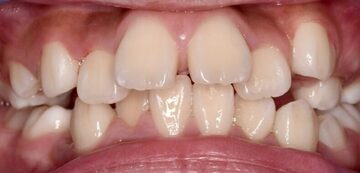

「うちの子、歯並びが少しガタガタしているけど、まだ生え変わったばかりだから様子見で大丈夫かな?」 「子どもの歯並びって、いつから歯医者さんに相談すればいいの?」

お子様の歯並びについて、このようなお悩みや疑問をお持ちではありませんか? 歯並びの問題は、見た目だけでなく、全身の健康にも大きな影響を与える可能性があります。特に、顎の成長が活発な子どもの時期に適切な処置を行うことが、将来の美しい歯並びと健康な身体を育む上で非常に重要です。

現代の食生活は、昔に比べてやわらかい食べ物が増えました。これにより、噛む回数が減り、顎の骨が十分に発達しないお子様が増えています。顎が小さく狭いと、生えてくる永久歯が並ぶスペースが足りず、歯がガタガタになったり、出っ歯になったりする原因となります。